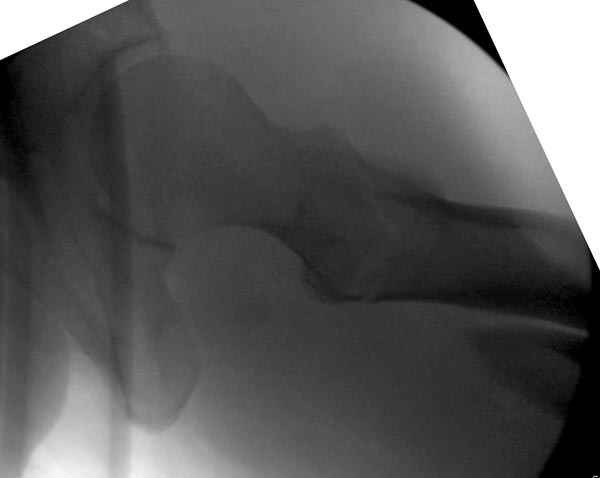

Второй случай тоже репозиция из малого доступа, больному 19 лет, множественные огнестрельные повреждениия конечностей, живота и черепа, правая конечность холодная, без пульсации. Ортопедический диагноз: огнестрельный перелом правого бедра. При срочной ангиографии повреждения сосудов не подтвердилось, конечность из-за ургентности состояния больного зафиксирована временным наружным фиксатором и больной оставлен на операционном столе для срочной лапаротомии хирургической службой.

Больной долго оставался нестабильным, только на 14 день удалось заменить на антеградный интромедуллярный штифт TFN (trochanteric femoral nail) SmithNephew. После неудачной попытки закрытой репозиции, несмотря на использование "joystick", проксимальный стержень от

наружного фиксатора, (перелом начал срастаться) репозицию провели из малого доступа, затем остальные этапы операции.

Случай был представлен из-за того, что больного оперировали после наружной фиксации и был риск инфекцирования через места проведения стержней (на снимках), прошло больше 3 месяцев, выписан из амбулаторной службы из-за отсутсвия надобности дальнейшего наблюдения.